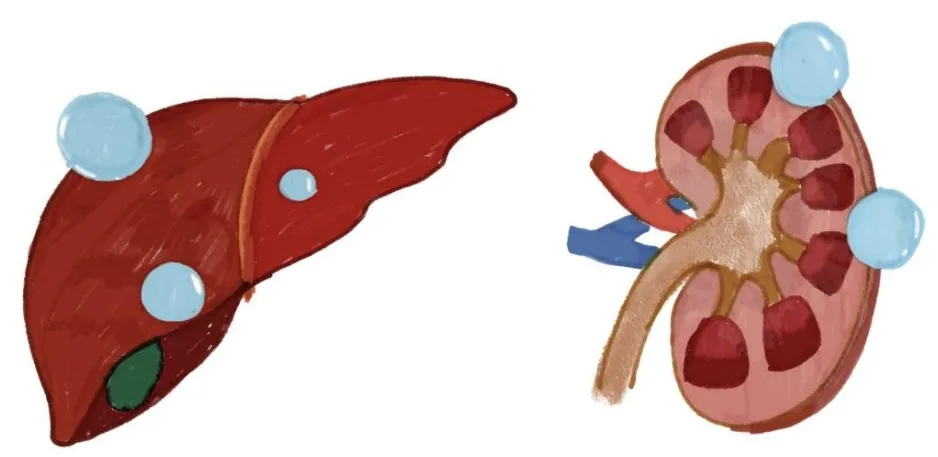

这两个小家伙,一个藏在肝脏里,一个躲在肾脏中,平时悄无声息,很多时候都是在体检时偶然被发现。

肝肾囊肿其实是一种很常见的良性病变,发病率较高。大多数囊肿都比较小,不会引起任何症状,就像是身体里的“小水泡”。但是,当它们长大到一定程度时,就开始不甘寂寞,搞出一些小动作来刷存在感了。

1.肝囊肿直径>5cm,肾囊肿直径>4cm的单纯性囊肿,可为单发或多发。

2.肝、肾囊肿引起明显临床症状者,如上腹不适、腹痛、血尿、腰背酸痛等。

3.压迫周围脏器引起继发性合并症者:如胆道梗阻、胃肠梗阻、肾盂积水等。

4.多囊肝、多囊肾较大囊肿造成压迫症状或引起肝、肾功能异常,需要临床干预治疗者。

5.囊肿合并感染者。